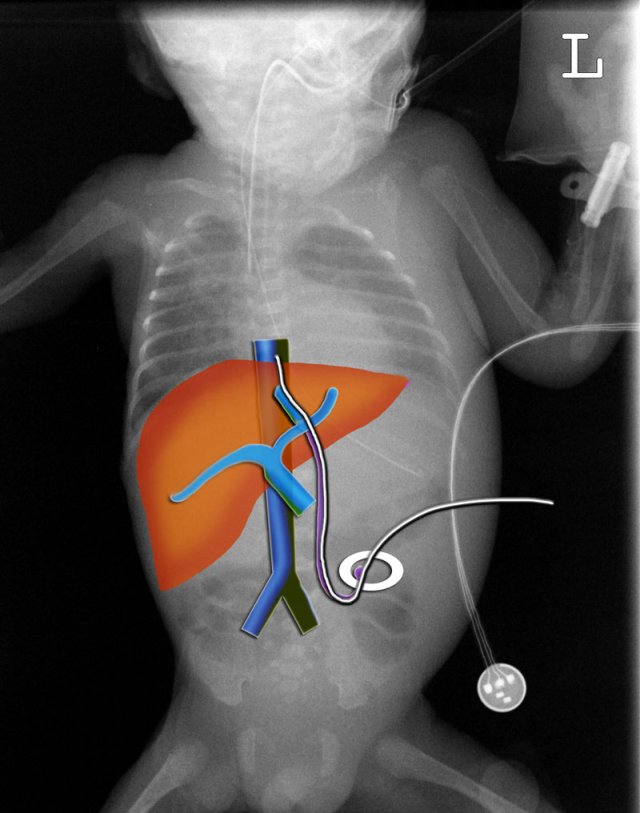

Umbilical vein catheter

An umbilical vein catheter should pass through the umbilic vein into the left portal vein.

Then through the ductus venosus into a hepatic vein and the inferior caval vein (IVC).

The tip should be positioned in the IVC at the level of the diaphragm.

Several line malpositions are possible:

• Low position in the umbilical vein.

Not all medication can be administered through a line in this position.

• Intrahepatic into the portal venous system, both right and left, or even into the superior mesenteric or splenic vein.

This can cause thrombosis.

• Perforation of the portal vein can cause haemorrhage or abscess formation in the liver.

• Position too deep in right atrium or in the left atrium through a patent foramen ovale or atrial septal defect.

This can lead to cardiac arrhythmias or perforation.